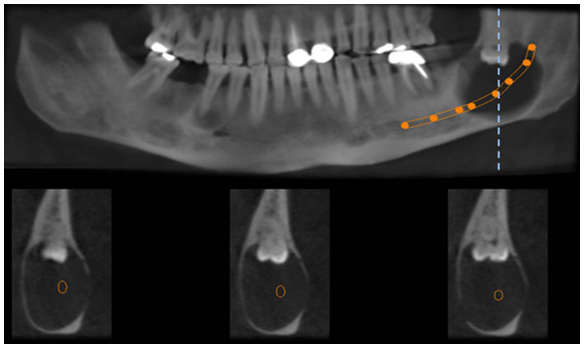

A CBCT was performed to identify the extension of the lesion and its relation with the IAC. Panoramic reconstruction (Figure 2A & 2B) shows a well-defined low density unilocular lesion circumscribing the crown of tooth #38 located vertically from the mid ramus extending below the level of the IAC, horizontally it extend from the apical third of the mesial root of #37 till the mid portion of the ascending ramus. Axial cuts (Figure 3) show expansion of the alveolar process and thinning and interruption of both lingual and buccal cortical plates. The roots of #37 show no resorption. The lesion is attached to tooth #38 at the level of the CEJ (Figure 4). The ectopic position of the IAC is also seen very clearly in the maximum intensity projection panoramic reconstruction (Figure 2B) and in the cross sectional images which shows the canal within the lesion (Figure 5A & 5B). After clinical and radiographic examination, a provisional diagnosis of dentigerous cyst was made; however, kerato cyst odontogenic tumor, amleloblastoma, ameloblastic fibroma were also considered in the differential diagnosis. Keratocyst don’t expand the bone to the same degree as presented here and attachment to the teeth will be more apically. Ameloblastic fibroma usually occurs in young patients which is not the case. Ameloblastoma would have presented internal septa if big in size as in this case. The most probable diagnosis is dentigerous cyst. The operation was performed under local anesthesia. Incision was made followed by raising a full thickness buccal mucoperiosteal flap. The lesion was then identified and the canal was viewed and confirmed, as seen on CBCT, to be passing in the center of the lesion. Dissection of the lesion away from the canal was performed using a tissue holder. With proper identification and isolation, the inferior nerve was preserved and the cyst was totally enucleated. Tooth number #38 was removed, and preservation of tooth #37. No sign of paresthesia was recorded after surgery. The surgical specimen was then sent for pathological analysis for final diagnosis. The histological examination showed a cystic lumen with blood content, a very thin lining of non-keratinized stratified squamous epithelium and dense fibro cellular connective tissue stroma with chronic inflammatory infiltrate. A macrophage and giant cell granuloma is noted around cholesterol crystals. There is no evidence of malignant change. The cyst opened measured 4x2x1 cm. A chronic inflamed dentigerous cyst was confirmed. Follow up CBCT was done after 3years of the surgery, and a progressive improvement in bone regeneration and healing process at the site of surgery was observed (Figure 6A & 6B); vitality test on tooth #37 response was positive.

Figure 5A Panoramic reconstruction with mandibular canal tracing; cross sectional images showing the position of the IAC within the lesion.